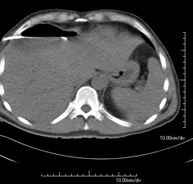

- Abdomen y pelvis- TC Abdomen Prueba diagnóstica que consiste en obtener imágenes del abdomen de alta definición anatómica (hígado, vesícula biliar, vía biliar, páncreas, bazo, estómago, intestinos, riñones, estructuras vasculares, vejiga, útero y ovarios, etc.) mediante el empleo de un equipo de TC (Tomografía Computarizada). Dichas imágenes se estudian posteriormente en una estación de trabajo que permite reconstrucciones bidimensionales en diferentes planos del espacio, y también reconstrucciones 3D (volumétricas). La mayoría de estudios requieren el empleo de contraste yodado para mejorar la definición de las imágenes. Prueba diagnóstica que consiste en obtener imágenes del abdomen de alta definición anatómica (hígado, vesícula biliar, vía biliar, páncreas, bazo, estómago, intestinos, riñones, estructuras vasculares, vejiga, útero y ovarios, etc.) mediante el empleo de un equipo de TC (Tomografía Computarizada). Dichas imágenes se estudian posteriormente en una estación de trabajo que permite reconstrucciones bidimensionales en diferentes planos del espacio, y también reconstrucciones 3D (volumétricas). La mayoría de estudios requieren el empleo de contraste yodado para mejorar la definición de las imágenes.

- TC Abdominopélvico Prueba diagnóstica que consiste en obtener imágenes bi y tridimensionales del abdomen y de la pelvis de alta definición anatómica (estructuras óseas, estructuras vasculares, hígado, páncreas, vesícula biliar, riñones, glándulas suprarrenales, bazo, intestino delgado y grueso, vejiga, útero y ovarios, próstata y vesículas seminales, uréteres, etc.) mediante el empleo de un equipo de TC (Tomografía Computarizada). La mayoría de estudios requieren el empleo de contraste yodado. Prueba diagnóstica que consiste en obtener imágenes bi y tridimensionales del abdomen y de la pelvis de alta definición anatómica (estructuras óseas, estructuras vasculares, hígado, páncreas, vesícula biliar, riñones, glándulas suprarrenales, bazo, intestino delgado y grueso, vejiga, útero y ovarios, próstata y vesículas seminales, uréteres, etc.) mediante el empleo de un equipo de TC (Tomografía Computarizada). La mayoría de estudios requieren el empleo de contraste yodado.